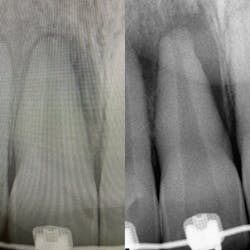

The postoperative visit and radiograph with the periodontist on July 28, 2022, showed the tooth was actually filling in with bone! See comparison periapical radiographs, original and new side by side, in Figure 6.

The reevaluation treatment notes from the periodontist were brief, reporting healing as “WNL” (I mean really, what is normal?)—no signs of infection or inflammation and the periapical was exposed indicating “significant bone fill.” Bryan’s next reevaluation appointment is scheduled for December 2022.